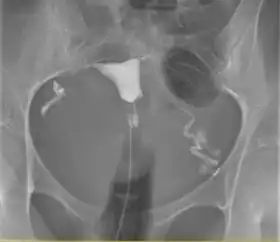

![]() A normal hysterosalpingogram. Note the catheter entering at the bottom of the screen, and the contrast medium filling the uterine cavity (small triangle in the center). | |

Hysterosalpingography (HSG), also known as uterosalpingography,[1] is a radiologic procedure to investigate the shape of the uterine cavity and the shape and patency of the fallopian tubes. It is a special x-ray procedure using dye to look at the womb (uterus) and fallopian tubes.[2] In this procedure, a radio-opaque material is injected into the cervical canal, and radiographs are taken. A normal result shows the filling of the uterine cavity and the bilateral filling of the fallopian tube with the injection material. To demonstrate tubal patency, spillage of the material into the peritoneal cavity needs to be observed. Hysterosalpingography has vital role in treatment of infertility, especially in the case of fallopian tube blockage.

The procedure involves x-rays (fluoroscopy).[7] Images are taken to demonstrate the filling of endometrial cavity, which shows full view of the fallopian tubes demonstrating the spillage of contrast material into peritoneum, the extent of the block if no spillage is present, or a delayed view in the case of abnormal cavities (locule) within. Subject may have vaginal spotting for one to two days, accompanied with pain that may persist for up to two weeks. Some medical centres routinely give prophylactic antibiotics before subject is allowed home.[3]